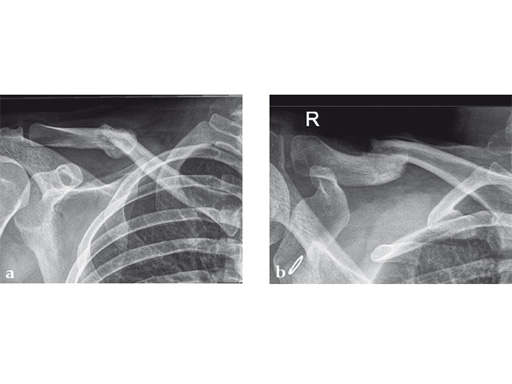

Case 2: a 29-year-old man sustained a midshaft clavicle fracture while playing soccer.

Case provided by Norbert Sdkamp and Martin Jaeger, Freiburg, Germany